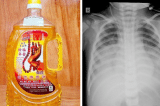

Uống nhầm dầu thắp đèn, bé 15 tháng tuổi suy hô hấp, nguy kịch

Sau khi uống phải dầu thắp đèn, bé 15 tháng tuổi tại Nghệ An tím tái, khó thở, rơi vào tình trạng nguy kịch dù nhanh chóng được đưa đi cấp cứu.